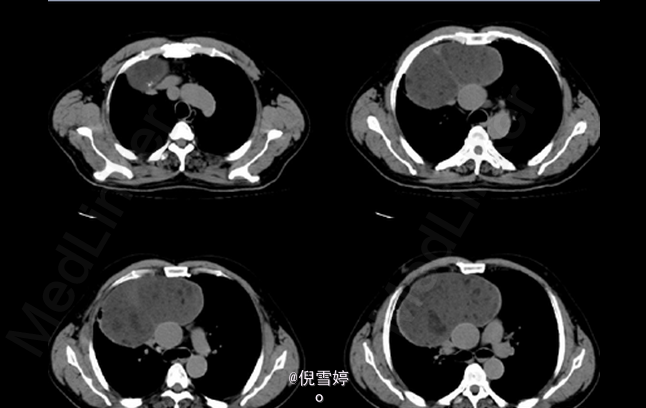

患者,男,49岁岁,因胸部不适2d就诊

患者除胸部不适外并无其他明显症状 辅查CT,右前纵隔囊性占位,多发脂肪样密度,病理检查良性

畸胎瘤 处理:手术切除